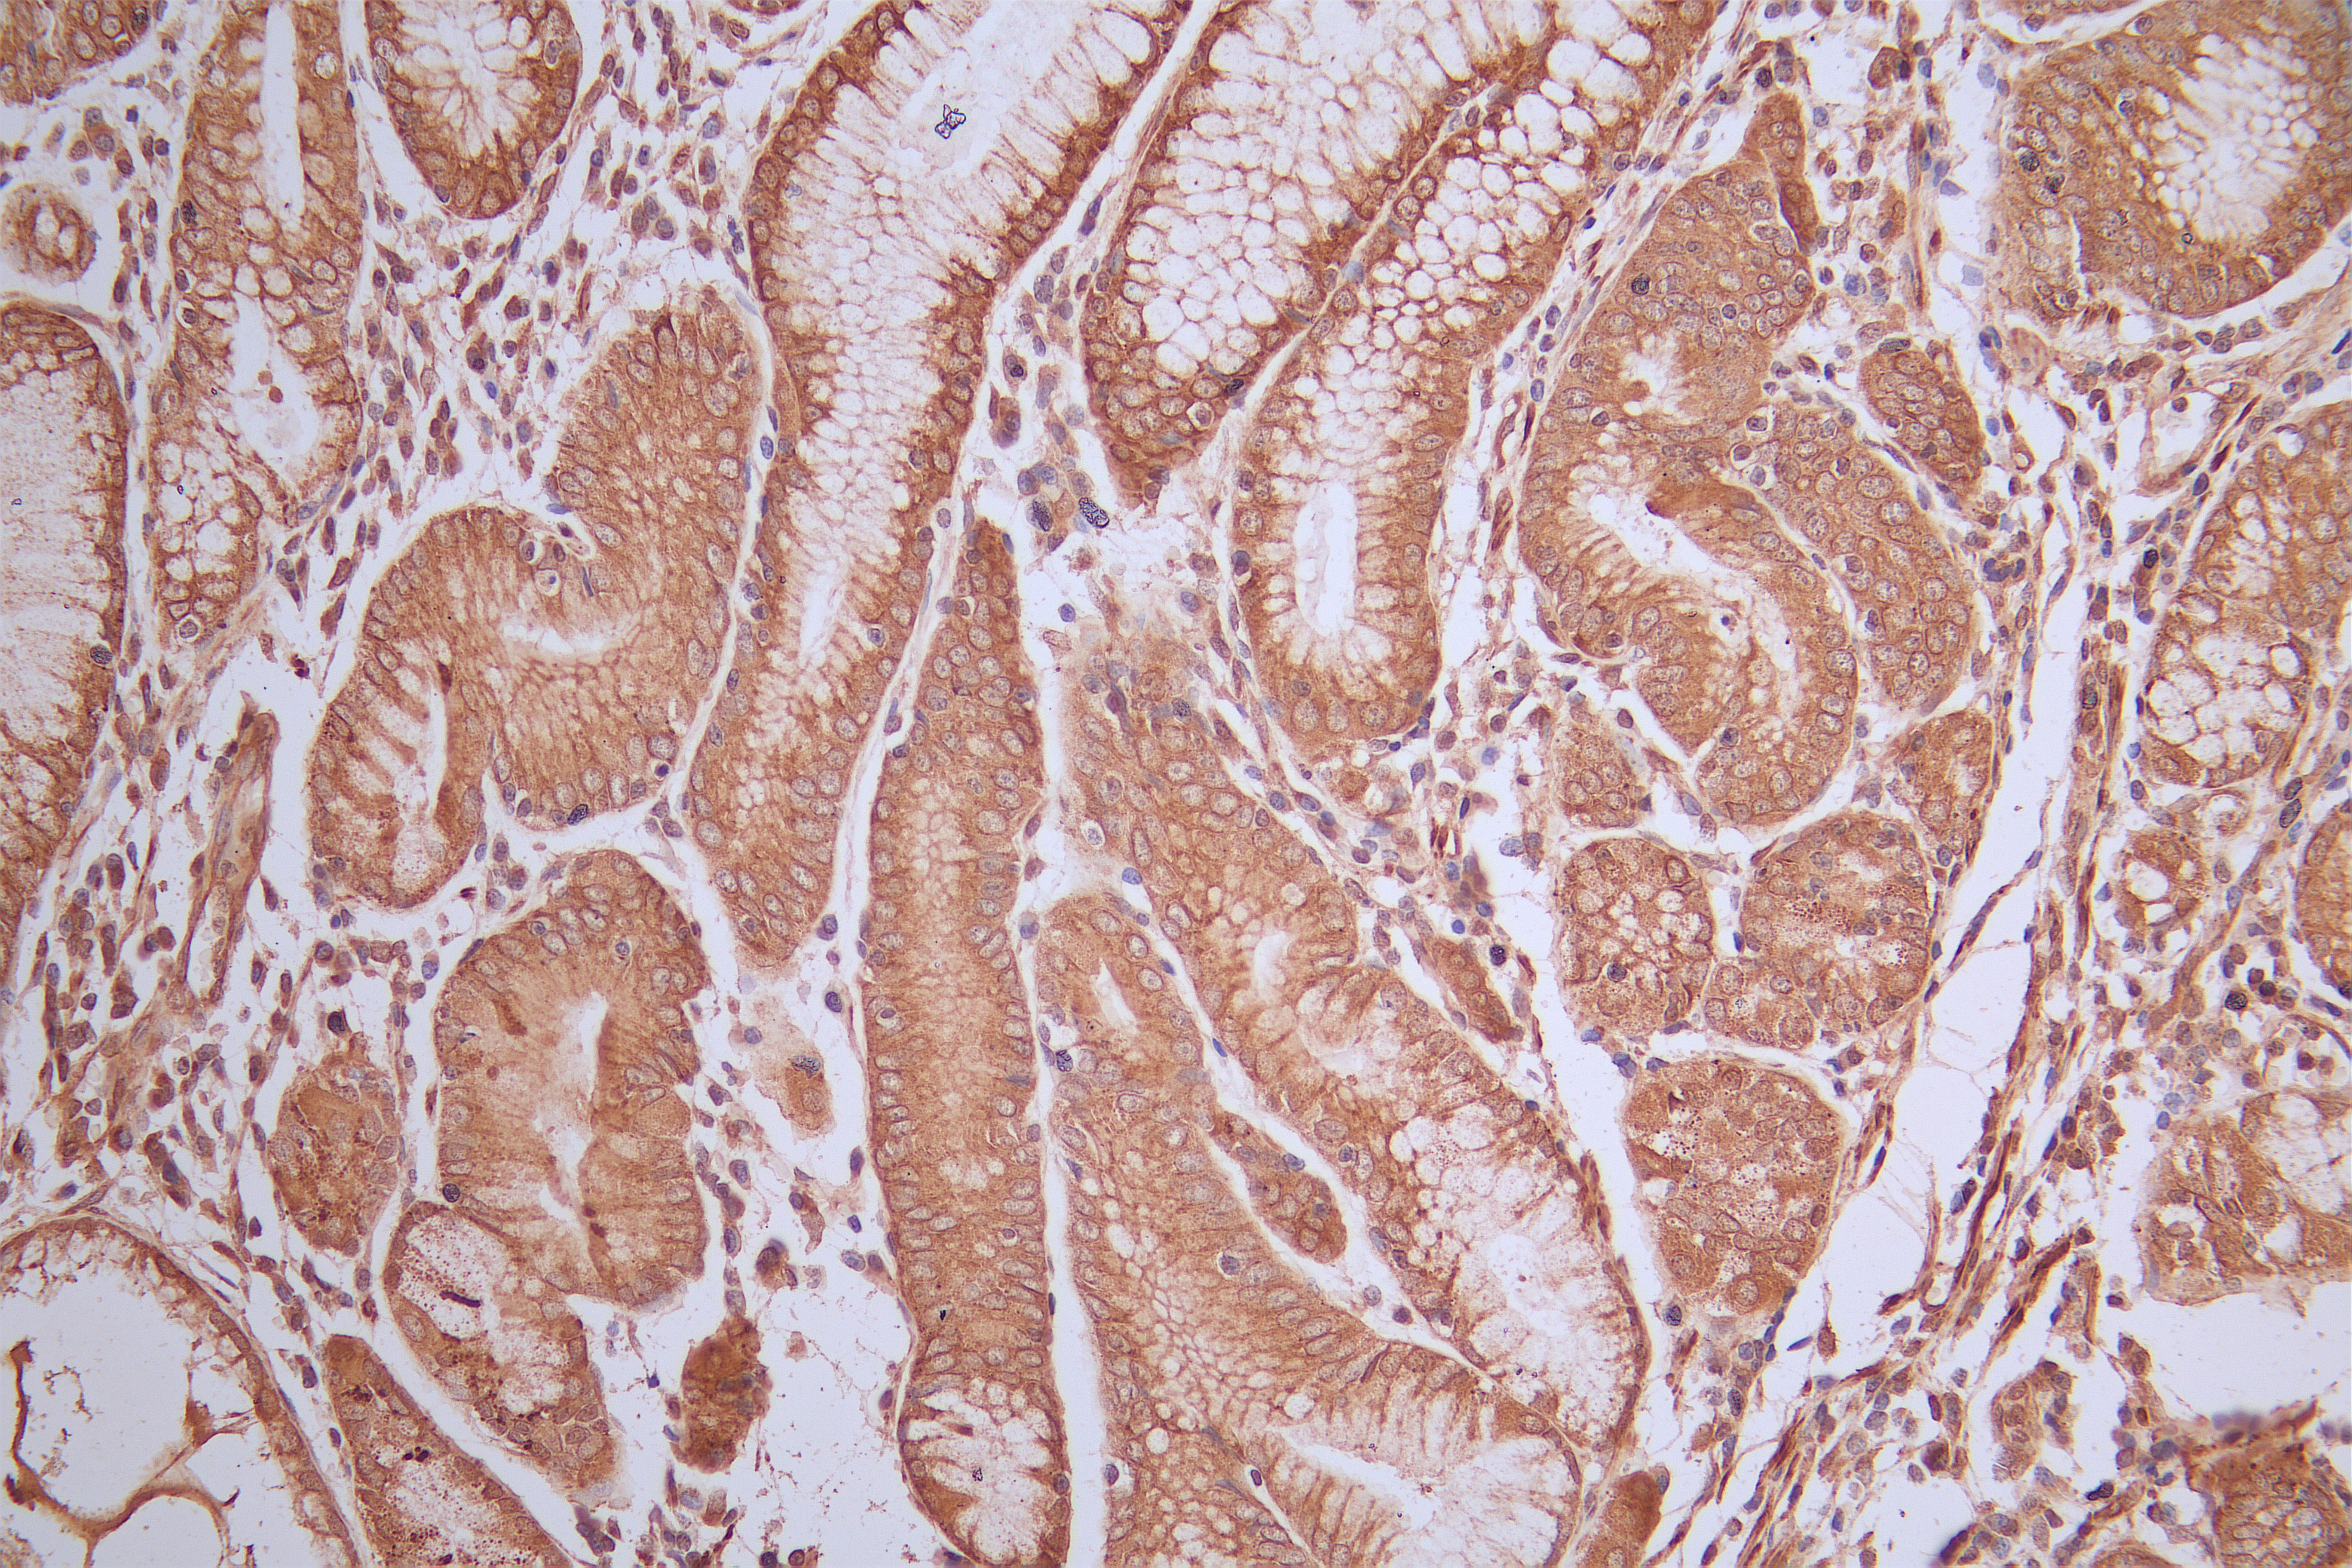

IHC image of CSB-PA019212LA01HU diluted at 1:50 and staining in paraffin-embedded Gastric cancer tissue After dewaxing and hydration, antigen retrieval was mediated by high pressure in a citrate buffer (pH 6.0). Section was blocked with 10% normal goat serum 30min at RT. Then primary antibody (1% BSA) was incubated at 4°C overnight. The primary is detected by a Goat anti-rabbit polymer IgG labeled by HRP and visualized using 0.05% DAB.